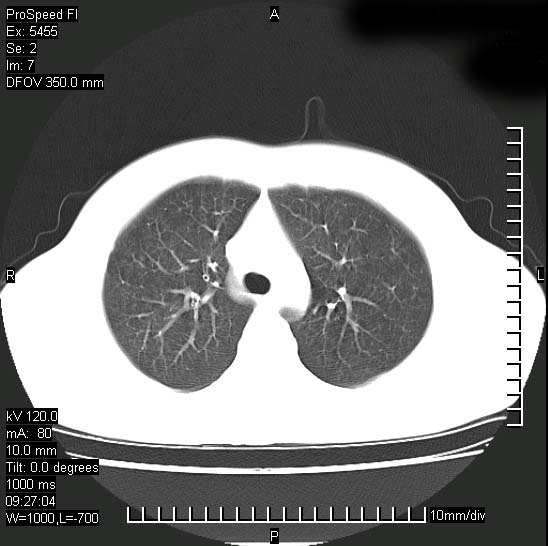

以下是引用zjzjr在2008-12-3 20:50:00的发言:[br]考虑泛细支气管肺炎,建议进一步检查除外肺出血性疾病如含铁血黄素沉着症、肺肾综合征等。

以下是引用zjzjr在2008-12-3 20:50:00的发言:[br]考虑泛细支气管肺炎,建议进一步检查除外肺出血性疾病如含铁血黄素沉着症、肺肾综合征等。

以下是引用光线在2008-12-3 20:19:00的发言:[br]双肺间质性改变。